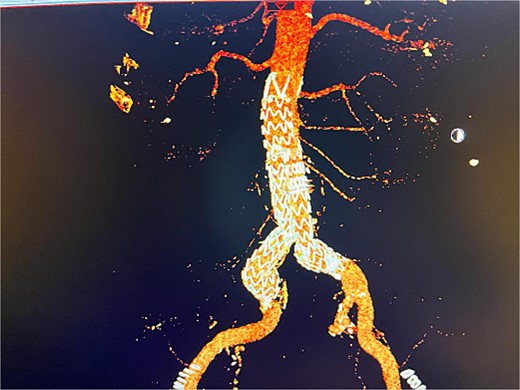

Despite these interventions, the patient experienced further episodes of acute limb ischemia (Fig. 4), leading to thrombolytic therapy a month later. This recurrence prompted a reevaluation of the treatment strategy. We considered extending the graft limb, which would involve sacrificing the hypogastric artery, or using an iliac artery extension with an iliac side branch. We ultimately chose the latter and implanted an E-iliac stent graft (Jotec ISB system) (Fig. 5a and b). Preservation of the hypogastric artery was prioritized, although extending into the external iliac artery would have been a viable alternative. However, the multidisciplinary team decided the preservation of the hypogastric artery would be more appropriate in this patient. The patient was discharged without anticoagulants.

(a, b) Intraoperative images showing implantation of the iliac side branch device ISB.

We believed the atheroma distal to the flared limb was the source of acute ischemia and subsequent embolization events. After 1 year of follow-up, the patient showed sustained improvement. Our treatment strategy focused on preserving the internal iliac artery while excluding disease in the common iliac artery using the iliac side branch system.